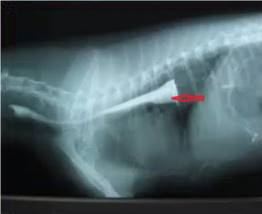

犬食道硫酸钡造影X线片提示( )。

食道阻塞

B